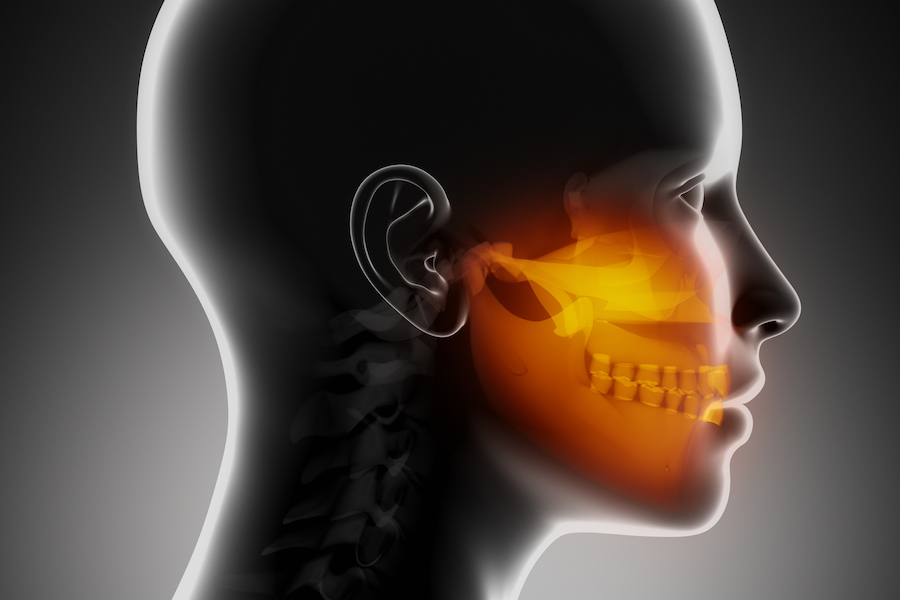

TEMPOROMANDIBULAR JOINT DISORDERS

The temporomandibular joints (TMJ) are the joints which allow us to talk...